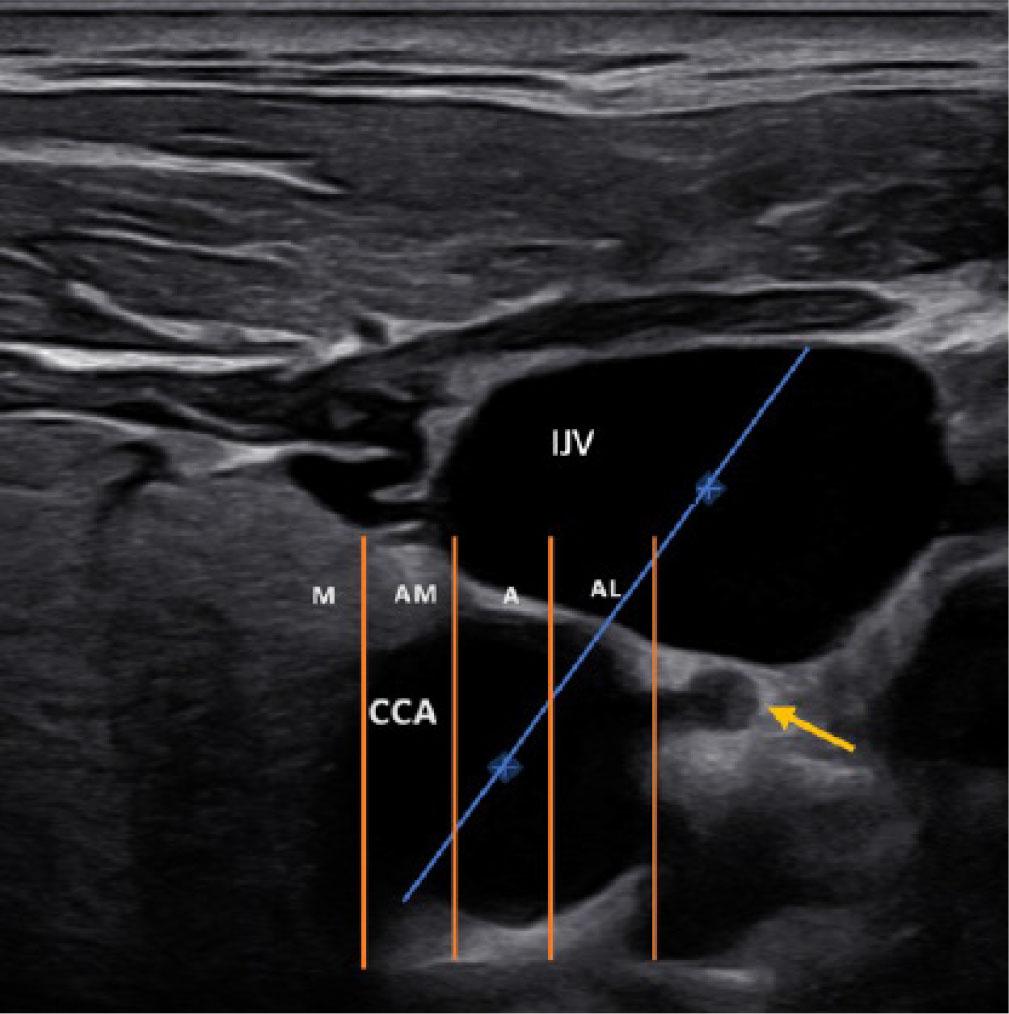

Fig. 1.

Fig. 2.

Fig. 3.